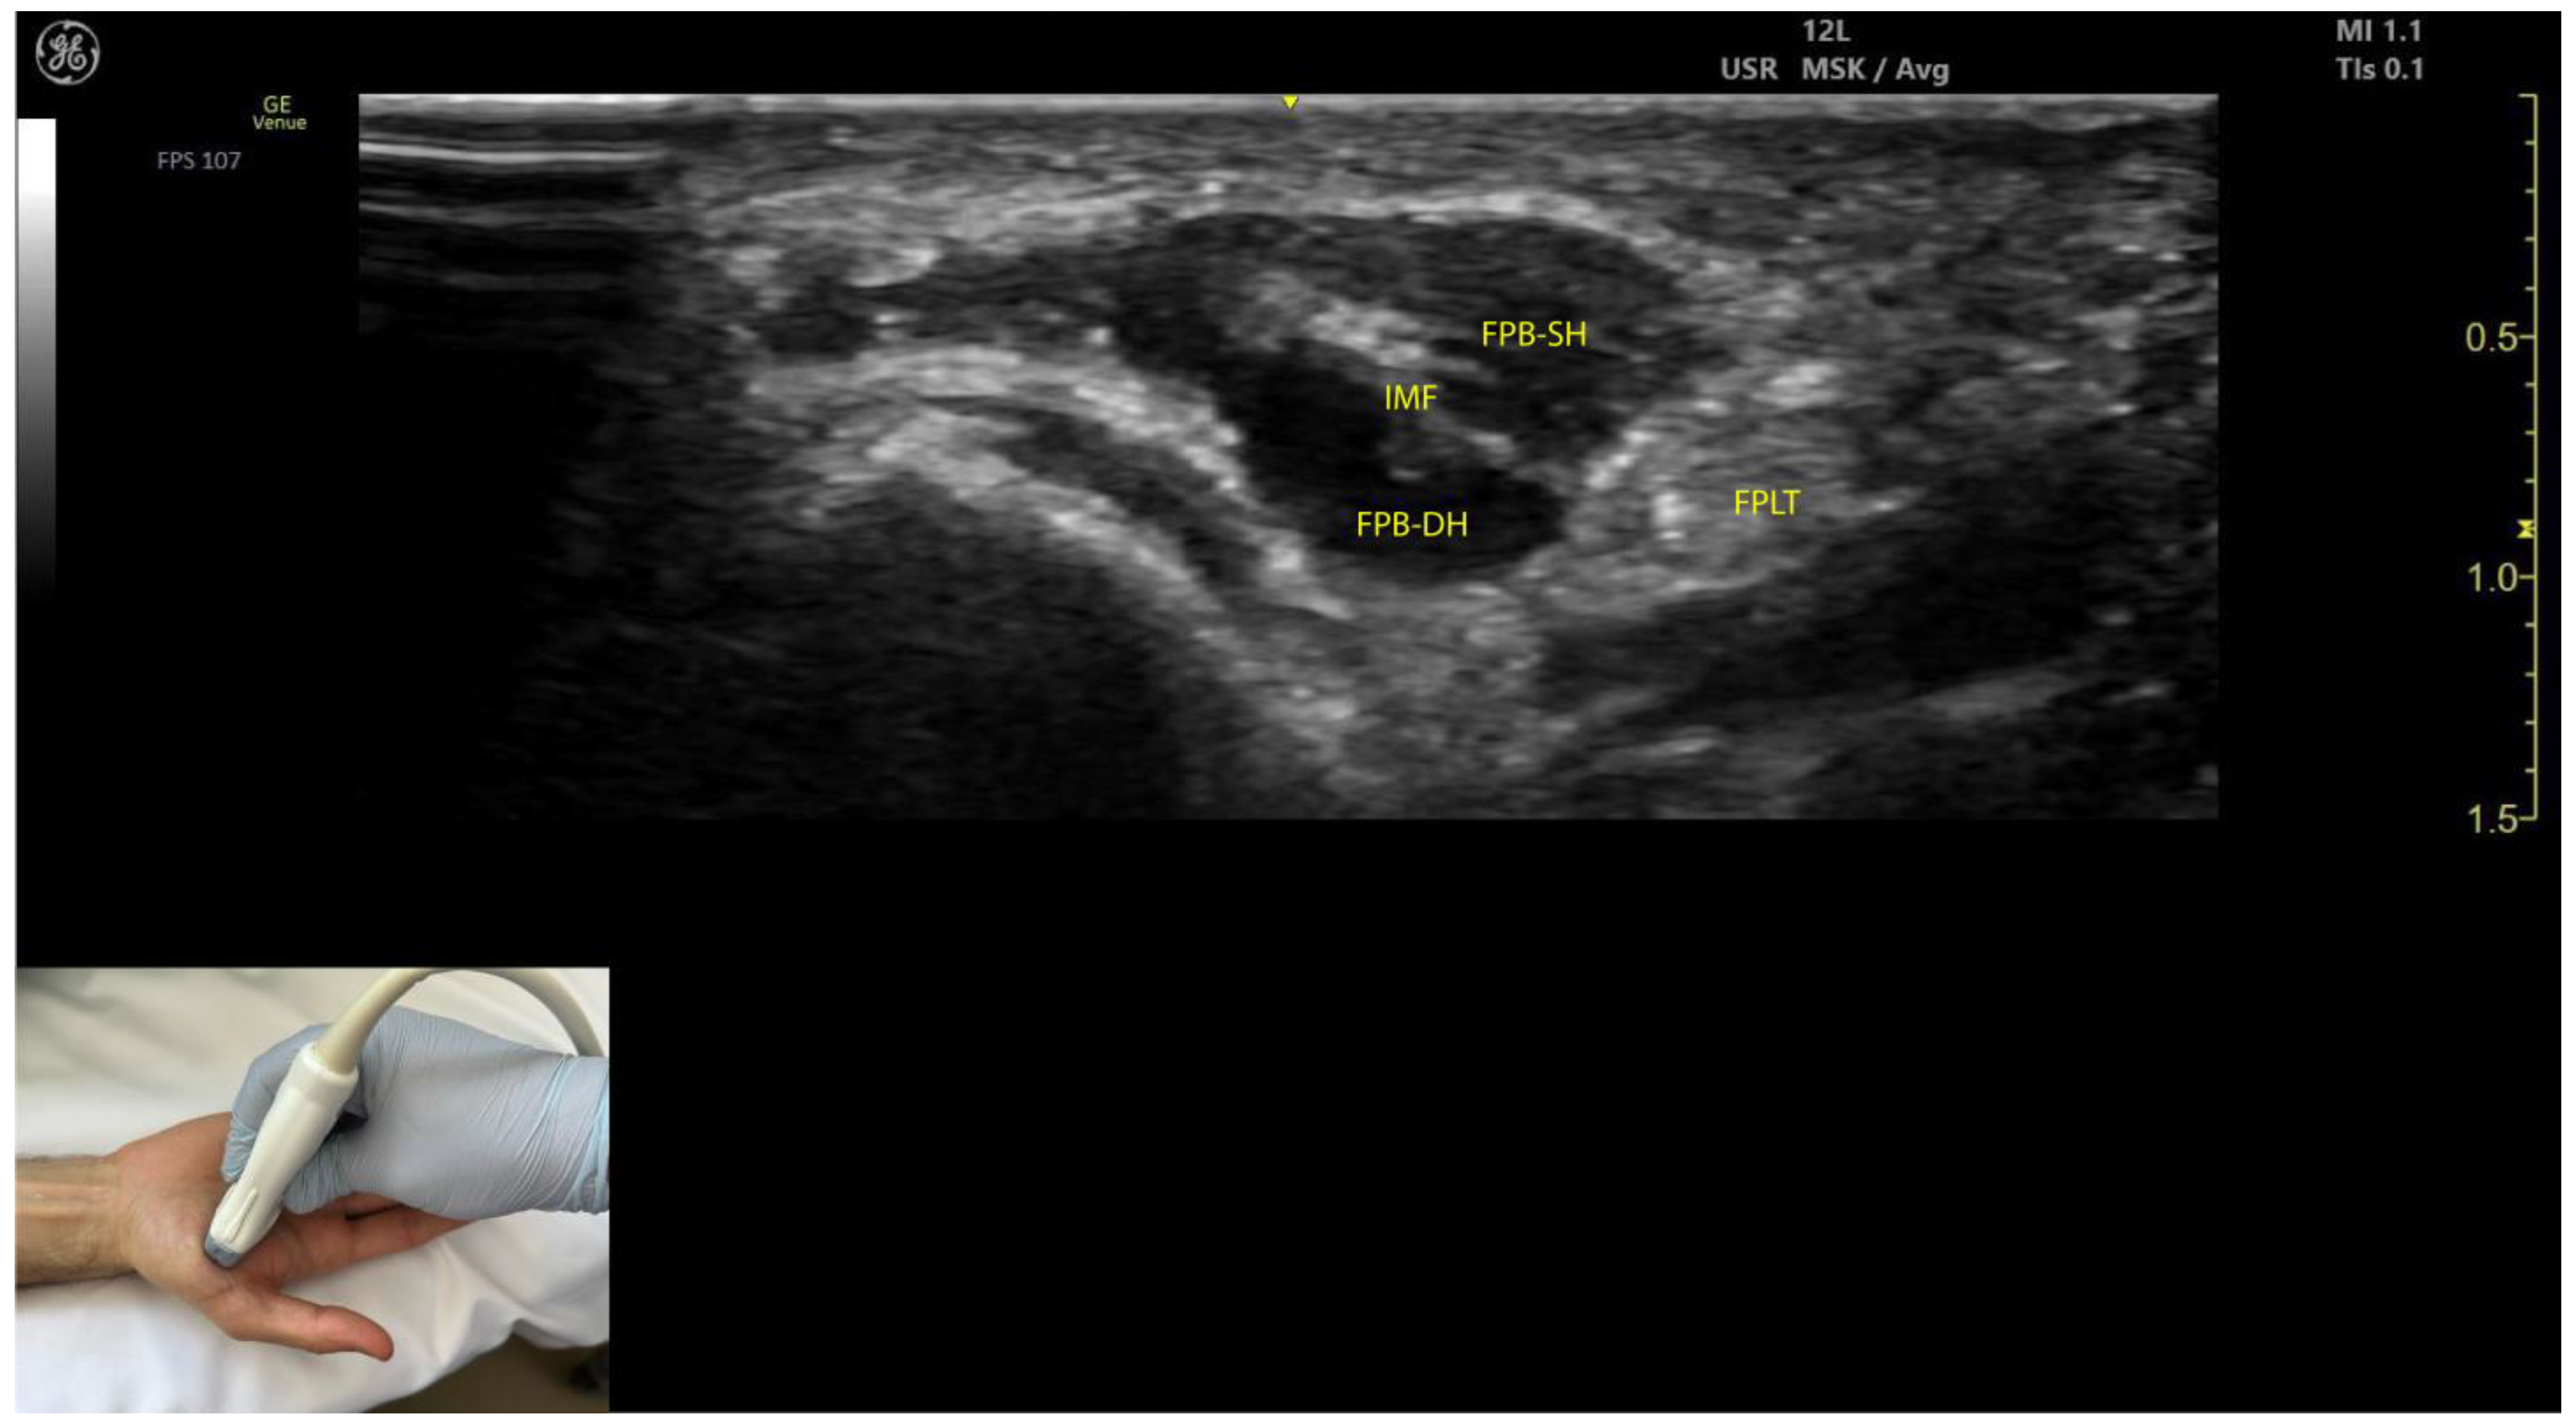

2.10.3. Key Ultrasound Landmarks (Figure 9)

- Muscle position: The FPB is the most medial muscle mass within the thenar eminence. It is situated medial to the APB and opponens pollicis and lateral to the adductor pollicis [56].

- Internal fascia: The FPB contains intramuscular fascia that separates its two heads—the superficial and deep heads—which can be targeted individually during injections [53];

- FPL tendon: Scanning toward the MCP joint reveals the FPL tendon located lateral to the superficial head of the FPB and deep to its deep head.

- External fascia: The FPB muscle lacks a pronounced fascia to clearly separate it from adjacent muscle masses, such as the abductor pollicis brevis and opponens pollicis, which may complicate precise localization during BoNT-A injections.

- Dynamic evaluation: Contraction of the FPB is observed during thumb flexion at the CMC and MCP joints [48].

2.10.4. Clinical Implications and Injection Strategy

- The region with the highest density of intramuscular nerve arborizations of the FPB is located 50–70% along the line connecting the hook of hamate to the head of the first metacarpal [51].

- In our clinical practice, the FPB is targeted for BoNT-A injections at the point of maximum muscle thickness, as determined by ultrasound. The optimal injection site is typically located at the midpoint of the thenar eminence. Ultrasound guidance ensures precise toxin delivery and allows for individual targeting of the superficial and deep heads, minimizing the risk of complications.